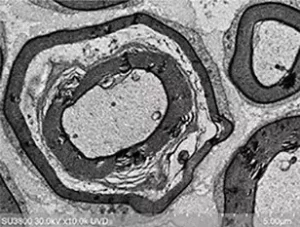

Kính hiển vi điện tử quét phát xạ trường Schottky SU5000